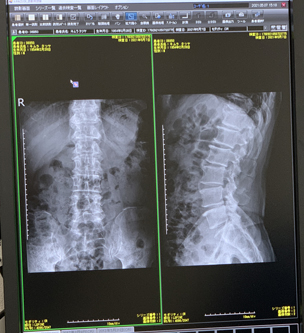

腰部のレントゲン検査をした。予想どうりX線画像には異常所見ない。これまでの経過から幹部の炎症が痛みの原因だろうから、X線画像にはなにも出ないと思うが、主治医はいちおう何も出ないことを確認するんだろうね。痛ければ鎮痛剤服用して日常生活動作を積極的にやったほうが早く良くなる。動かないと痛いことが長引く。ということだ。主治医の様子から整形外科的に大きな問題のある症例ではないことが読み取れる。まあ、痛いけど、一安心。